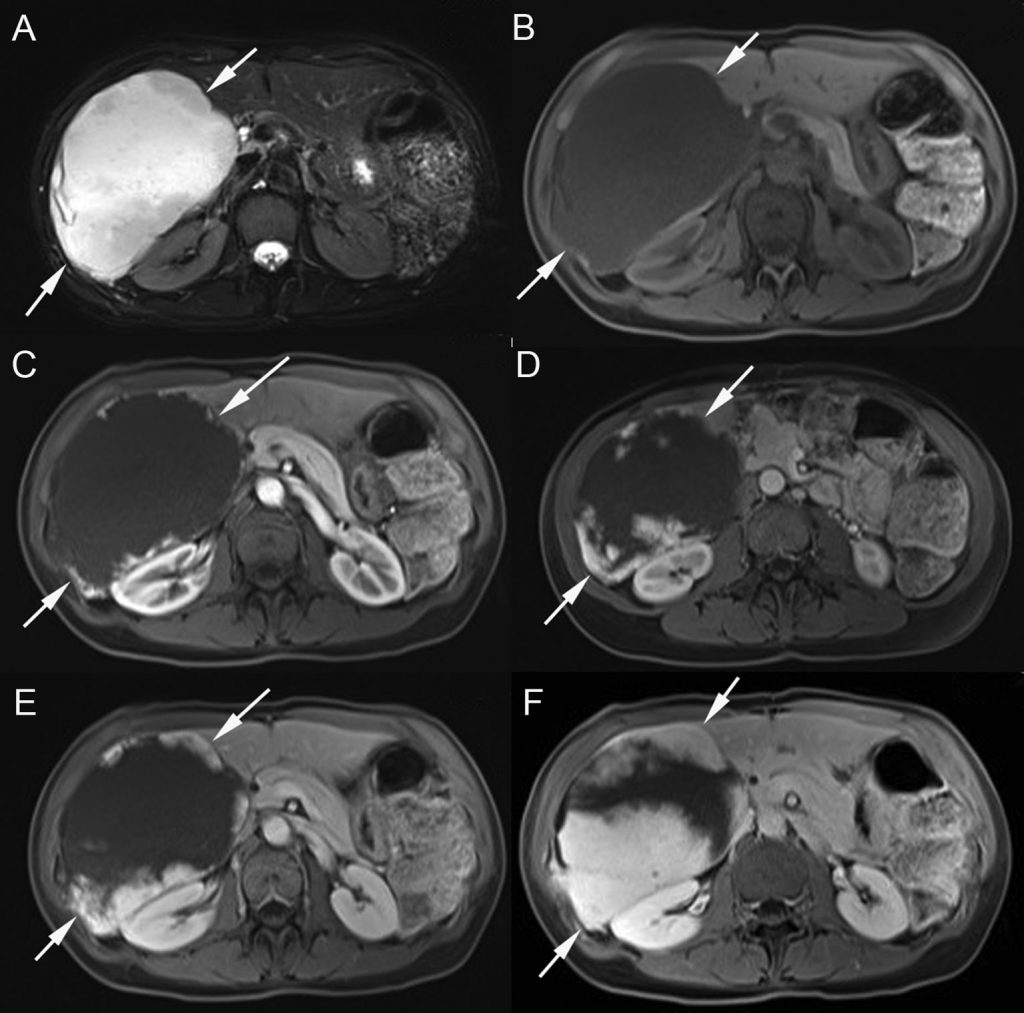

Au scanner, la lésion est bien limitée et très hypodense avant injection. L’IRM montre une lésion généralement homogène, bien limitée, très hypo-intense sur les séquences en pondération T1 et qui a la particularité d’être très hyperintense sur les séquences en pondération T2 (figure 16.8).

Fig. 16.8. IRM d’un hémangiome du foie droit. En pondération T2, il apparaît en franc hypersignal, d’intensité proche de celle du liquide cérébrospinal (A). En pondération T1, il présente un hyposignal homogène avant injection de chélates de gadolinium (B). Après injection, sur les temps artériel (C), portal (D), tardif (E) et très tardif (F), des prises de contraste périphériques sont initialement discontinues, puis confluent progressivement les unes avec les autres pour réaliser un rehaussement complet de la périphérie vers le centre (centripète).

Source : CERF, CNEBMN, 2022.

Après injection de produit de contraste en échographie, au scanner ou en IRM, on observe un rehaussement caractéristique périphérique discontinu au temps artériel suivi d’une confluence des zones de rehaussement de la périphérie vers le centre au cours des minutes qui suivent l’injection (correspondant au remplissage progressif de proche en proche par le produit de contraste des lacs vasculaires) avec une persistance du rehaussement sur les temps tardifs (figures 16.7 et 16.8).